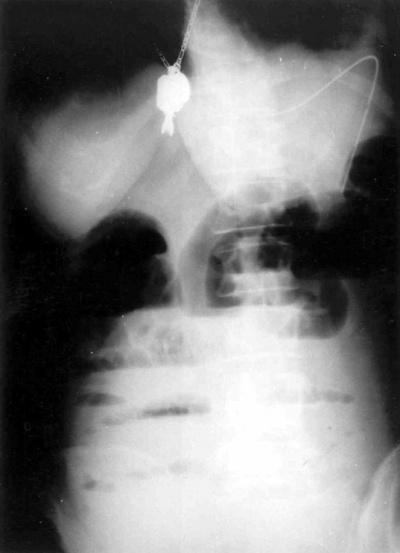

לעתים רחוקות, כדי לקבוע את גובה החסימה ואת מידתה בחולים הלוקים בחסימה דינמית, או כדי להבדיל בין שתי צורות החסימה, יש לצלם את החולה לאחר בליעת חומר ניגוד נספג מסוג גסטרוגרפין. בחסימה דינמית ניתן למצוא התקדמות של חומר הניגוד עד לחסימה (תצלום 6.4), ואילו בחסימה אדינמית ניתן למצוא אמנם מעבר לכל אורך המעי, אך מעבר איטי ביותר. לחולים שבהם יש חשד לחסימת הכרכשת, אין לתת בריום דרך הפה אלא לבצע חוקן בריום תחילה. ב- CT בטן עם חומר ניגוד ניתן לראות לולאות מורחבות שלאחריהן לולאות התמט, בצקת של הלולאות ונוזל ביניהם (תצלום 7.4).

בחולים הלוקים בחסימת מעי על-ידי אבן מרה החודרת למערכת העיכול אפשר להדגים את החסימה בעזרת חומר ניגוד (תצלומים 8.4 ו-9.4) או ב-CT (תצלום 10.4). בחולים הלוקים בחסימת מעי על-ידי פיטובזואר להדגים את החסימה בעזרת חומר ניגוד (תצלום 11.4) או ב-CT. התפשלות של המעי ניתנת להדגמה בצילום בריום או בטומוגרפיה ממוחשבת (CT) (תצלום 12.4 - 13.4)